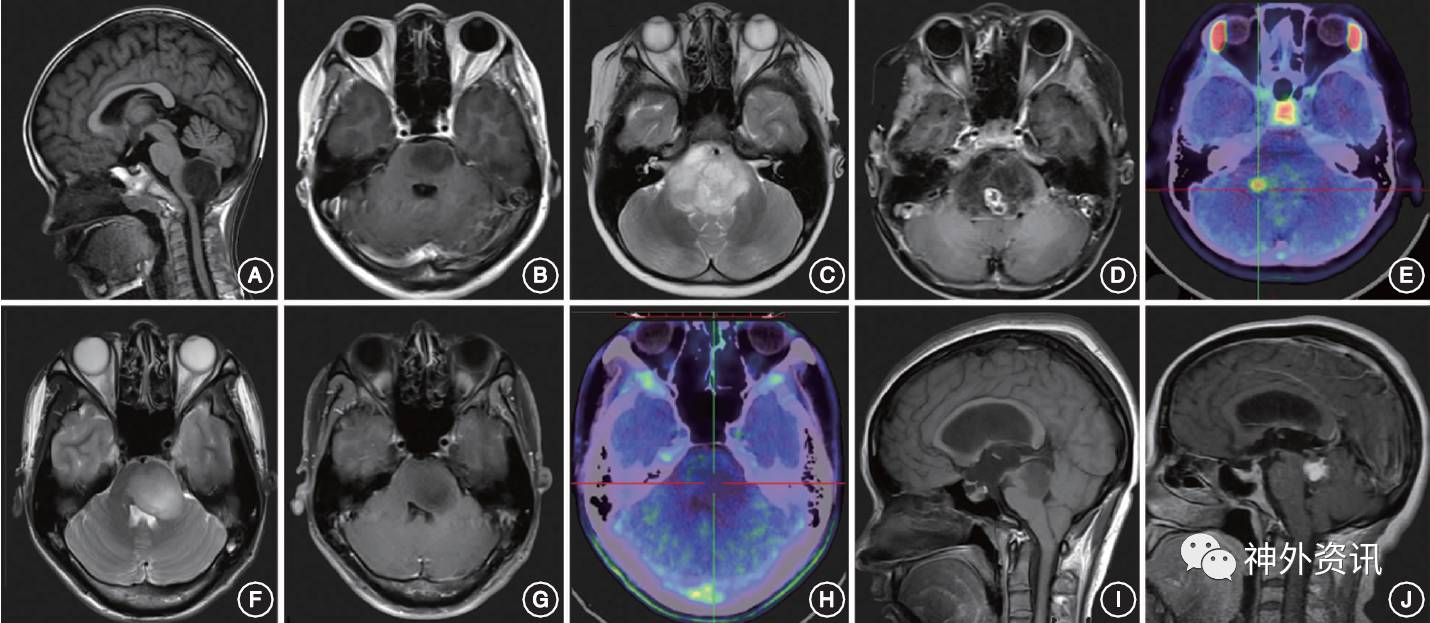

Ⅰ型:外生型BSG,肿瘤向外生长,主体位于脑干外部(图1A) 。

Ⅱ型:内生型BSG,可分为Ⅱa型即局灶内生型(图1B)和Ⅱb型即弥散内生型。对Ⅱb型BSG建议行11C-MET PET检查,综合MRI增强扫描的特点和 MET摄取情况,可将Ⅱb型肿瘤分为伴有局灶性强化或高代谢的Ⅱb1型(图1 C~E)和无局灶性强化或高代谢的Ⅱb2型(图1F~H)。

Ⅲ型:为特殊类型的BSG,Ⅲa型为顶盖胶质瘤(图1I);Ⅲb型为导水管胶质瘤,其发生率较低,以梗阻性脑积水为首发症状,病理类型以低级别胶质瘤为主(图1J);Ⅲc型为NF1相关的BSG,可分布在脑干内任何部位,可表现出各种生长方式和影像学特点。

图1. 基于MRI的脑干胶质瘤分型 A.外生型;B.局灶内生型;C-E.弥散内生型脑干胶质瘤伴有局灶强化和高代谢;F-H.弥散内生型脑干胶质瘤无局灶强化和高代谢(C、H为11C-MET PET-CT影像);I.顶盖胶质瘤;J.导水管胶质瘤。